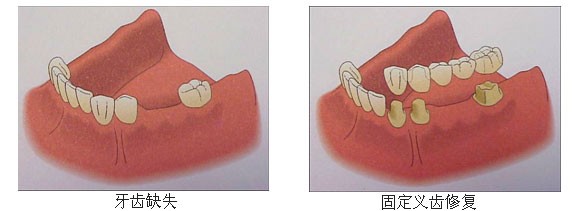

针对牙齿缺失,目前有三种方法可进行修复:活动义齿、烤瓷牙、种植牙。

烤瓷牙:单颗或少量缺牙可以通过烤瓷牙加以修复,但需要磨掉旁边正常的牙齿做为“烤瓷牙”支架。